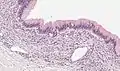

| Micrograph showing a mucinous cystadenoma of the ovary. H&E stain. | |

Mucinous cystadenoma is a benign cystic tumor lined by a mucinous epithelium. It is a type of cystic adenoma (cystadenoma).

Mucinous cystadenomas make up 15–20% of all ovarian tumors. They often become very large and can extend up into the abdomen.

These tumors are usually evaluated using ultrasound, CT scan, or MRI. Findings on imaging studies are nonspecific. These ovarian tumors are usually multi-septated, cystic masses with thin walls. They also contain varying amounts of solid tissue which consists of proliferating stromal tissue, papillae, or malignant tumor cells.

Benign mucinous cystadenomas compose 80% of mucinous ovarian tumors[2] and 20–25% of benign ovarian tumors overall. The peak incidence occurs between 30 and 50 years of age. Benign tumors are bilateral in 5–10% of cases.